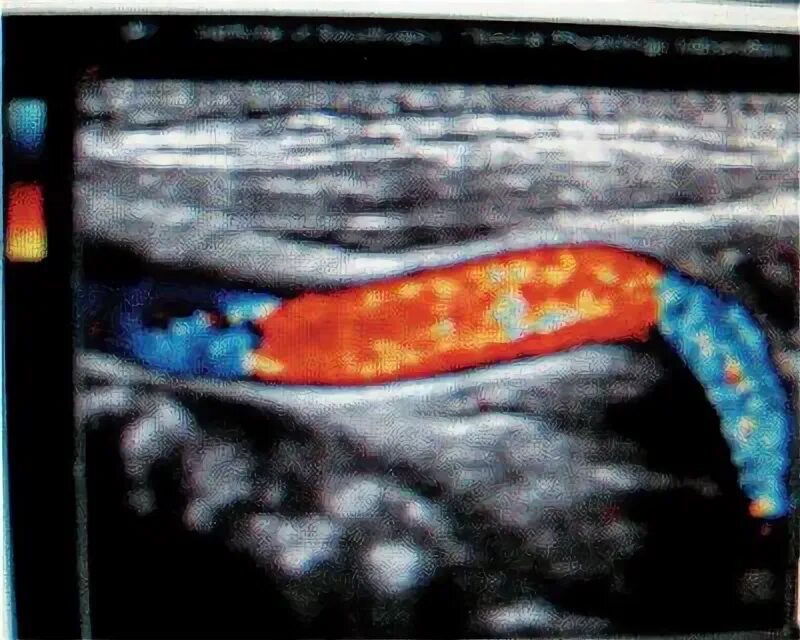

С образная извитость артерий